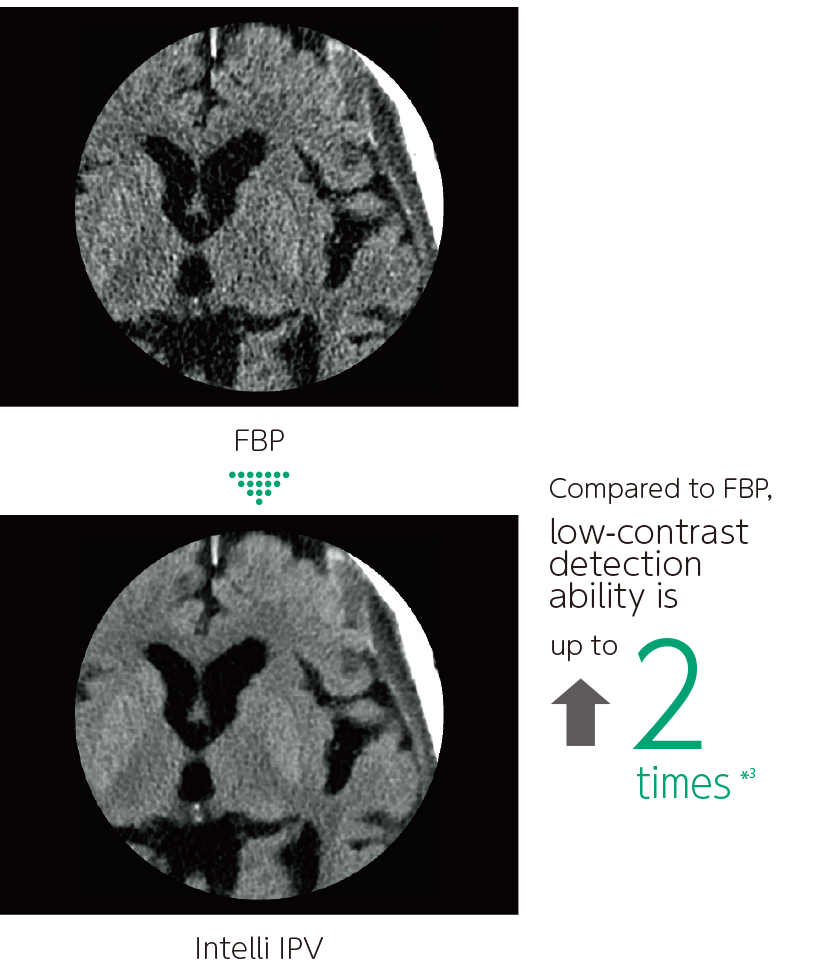

Intelli IPV is an image reconstruction technique developed with AI technology*1. Reconstruction processing has been speeded up by using images obtained through sufficient iterative processing as training data. Based on the Fujifilm's Visual Model, reconstruction processing using RawData brings the NPS (Noise Power Spectrum) closer to FBP (Filtered Back Projection) and keeps the image texture, even at a high noise reduction rate. It reduces image noise by up to 90%*2 and radiation exposure by up to 83%.*3 It also improves low contrast detectability by up to 2 times.*3

Improved low-contrast resolution